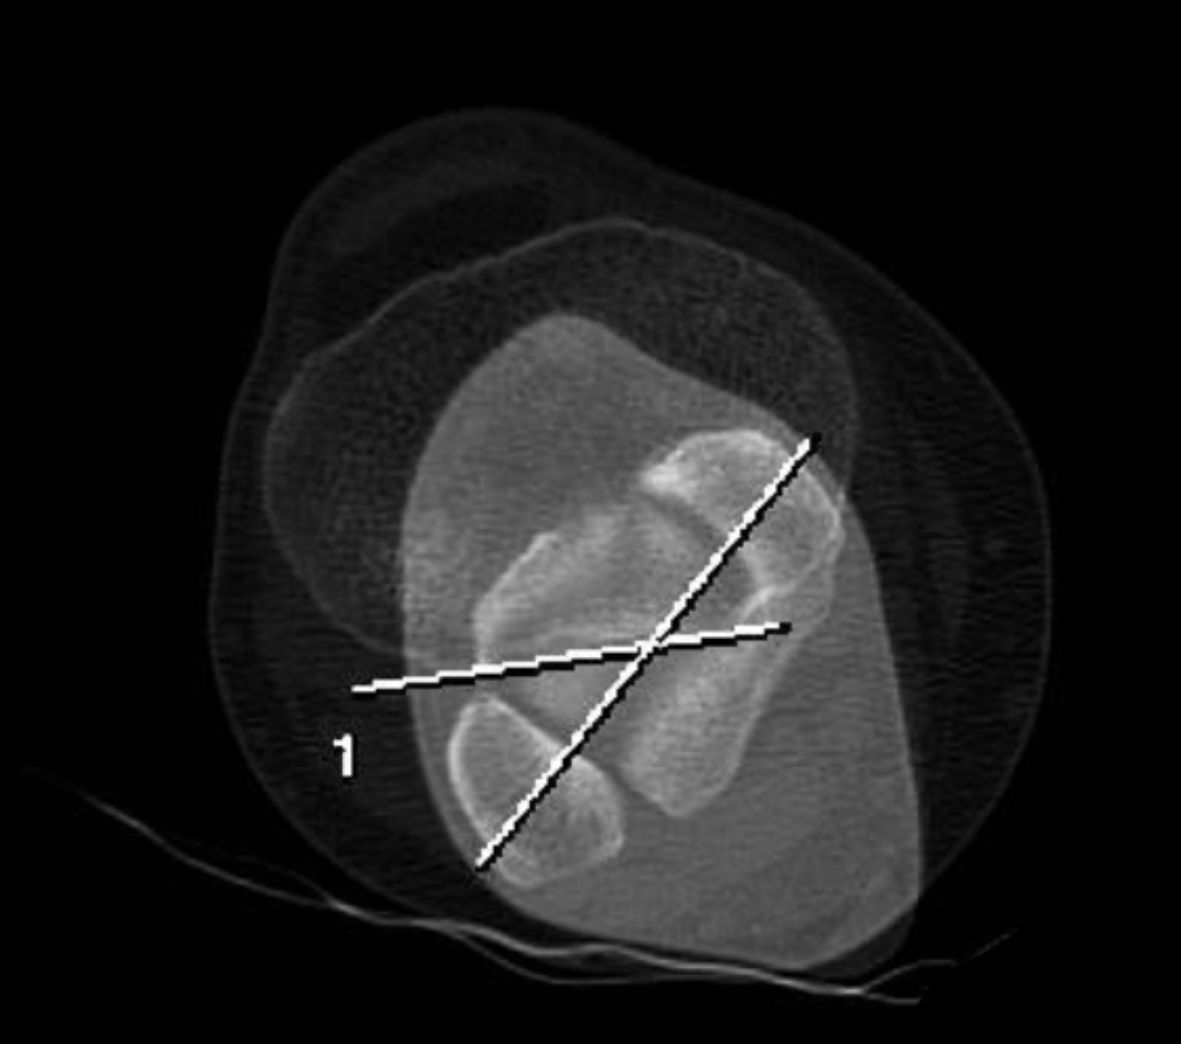

The TT-TG distance can be measured as the mediolateral distance between the midpoint of the insertion of the patellar tendon and the trochlear groove (Figure 1).

Tibial torsion is measured between a reference line tangential to the posterior border of the tibial plateau right above the tip of the fibular head, and with a second line that runs through the center of the medial and lateral malleolus [5]. (Figure 2)